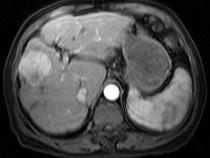

问题 男40岁肝区疼痛,消瘦乏力,腹部包块,AFP阳性,MR检查如图,最佳的诊断是哪一项()

选项 A.肝脓肿 B.肝血管瘤 C.肝腺瘤 D.肝肉芽肿 E.肝癌

答案 E